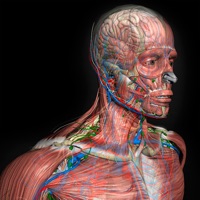

Explore a anatomia do corpo humano em todos os ângulos, de uma forma tridimensional e interativa. O aplicativo permite visualizar um modelo masculino* em 3D com todos os sistemas. (* o modelo feminino contido nesta versão inclui apenas o esqueleto e sistema reprodutor.) Em Português, Inglês, Espanhol e Latim (de acordo com a Terminologia Anatômica de 1998) - Novos comandos de toque: arraste 1 dedo para mostrar as legendas, 2 dedos para rotacionar o modelo, e 3 dedos para movê-lo -Agora com Realidade Aumentada (para IPhone6s ou superior) Este aplicativo foi projetado como um recurso adicional para o aprendizado de anatomia e não deve ser utilizado como fonte única de informação. Sistema incluídos: - esqueleto - musculatura contendo a origem e inserção - sistema nervoso - sistema circulatório (venoso e arterial) - sistema respiratório - ligamentos, cartilagens e articulações - sistema digestório - sistema urinário - sistema reprodutor - sistema linfático